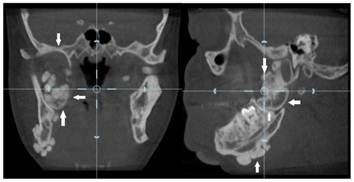

Figure 5

Coronal and sagittal section view of the right condyle showing large lobulated osteoma (white arrows)

Dental volumetric tomographic (DVT) images showed multiple osteomas of the buccal cortex of the right mandibular angle and left mandibular angle (Figure 3,4). Additionally, in the coronal and sagittal sections of the mandible condyle, a huge osteoma that limited mouth opening was diagnosed (Figure 5). Cephalometrically, he showed a slightly retrusive maxilla with an ANB angle of 1˚and a relatively normal mandibula in anterioposterior direction. His mandibular plane angle (S-N / Go-Me: 25˚) and articular angle (S-Ar-Go: 133˚) were reduced (Table 1). His profile was straight due to the slightly retruded maxilla position. According to the Steiner's S line his lips were in normal position (Figure 6). The osteomas were submitted for pathologic examination. Histopathologic examination revealed that the specimens displayed a normal-appearing dense compact lamellar bone with minimal marrow spaces and rare irregular Haversian canals that did not show osteoclasts or osteoblasts (H&E X100)(Figure 7). Due to the dental anomalies, the osteomas in the mandible and the familial history of the patient, the patient was diagnosed as GS. Following resection of the osteomas that caused discomfort, prosthetic rehabilitation was performed.

Osteomas are predominantly detected by routine panoramic radiography.15 Pain is rarely observed, and the disease is predominantly asymptomatic, but the lesions can cause facial asymmetry as a result of expansion.13 In addition to clinical palpation, dental panoramic radiography is an effective means of detecting multiple osteomas of the jaws that are characteristic of GS. Radiologically, the lesions are radio-opaque. In our patient, radio-opacities on the angle of the mandible were observed, and several impacted teeth in all segments of the jaws were evident. Increased difficulty of tooth extraction was present due to the high density of the alveolar bone, the limited mouth opening, and the loss of the periodontal space.16 Our diagnosis was performed by CT radiographs to detect osteomas and dental anomalies.